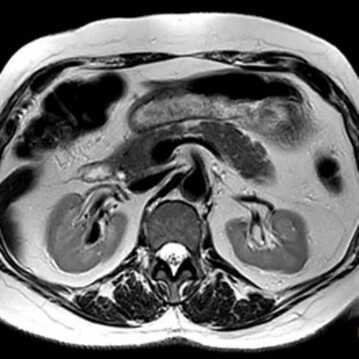

Die MRT (Magnetresonanztomographie), auch Kernspintomographie genannt, ist eine Untersuchung in einem Magnetfeld und benötigt keine Röntgenstrahlen. Mit ihr können alle Körperregionen überlagerungsfrei dargestellt werden. Wir führen hier die MRT fast aller Körperregionen, Organe und Blutgefäße durch.